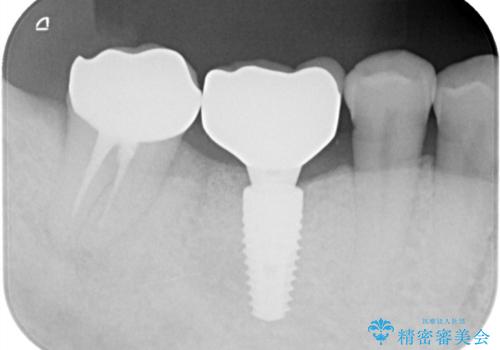

- 奥歯の欠損をインプラントで治療したいと来院された患者様です。

骨の状態が安定するまで待機したのち、インプラントを埋入しています。

スクリューリテインにて上部構造を連結しています。